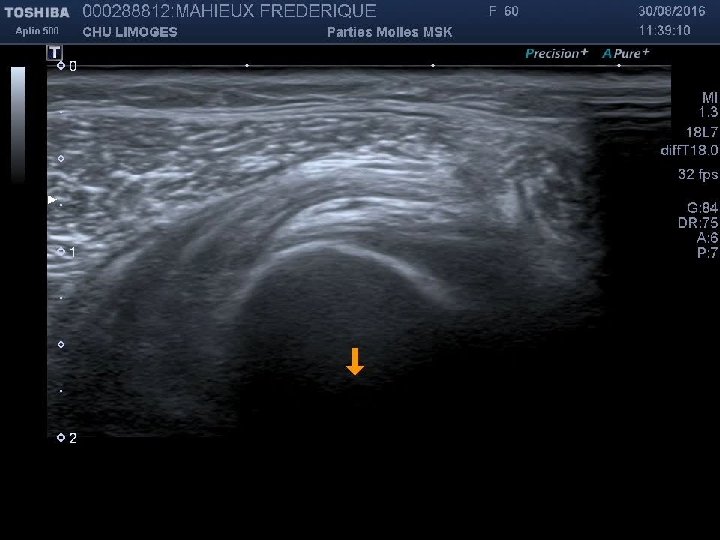

Cas clinique 4 • Footballeur de 28 ans, entorse de cheville à répétition, consulte pour des douleurs profondes postérieures associées à une instabilité. • A l’examen, douleur postérieure sans atteinte du tendon calcanéen. Laxité sagitale. • Radio: Pas de fracture Suspicion d’un syndrome du carrefour postérieur

Cas clinique 4 (suite): Buts de l’écho • Poser le diagnostic • Recher des facteurs de gravité • Guider le traitement

Infiltration du carrefour postérieur